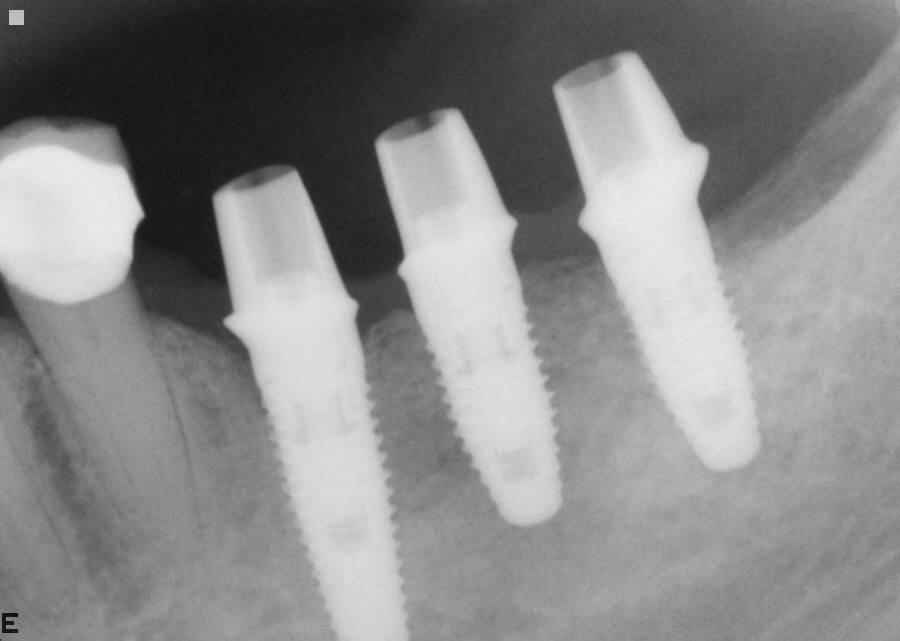

Dental Implants

Dental implants are prosthetic replacements for missing teeth. According to ICOI (International Congress of Oral Implantologists) there are commonly three parts to what it is described as an implant: the implant device which is predominantly made of titanium (which is inserted into the bone), the abutment, and a dental crown or a denture which are connected to the implant through the abutment.